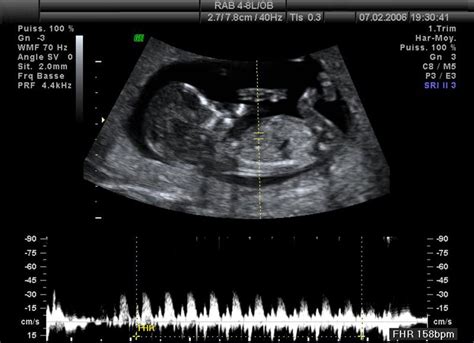

Tretí mesiac predstavuje koniec prvého trimestra. Dieťa je už oficiálne nazývané plodom. Maternica sa zväčšuje a na konci mesiaca je ju možné nahmatať nad lonovou kosťou. Plod rýchlo rastie, dosahuje dĺžku okolo 6-7,5 cm a váži približne 15 gramov. Hlava je stále neprimerane veľká, ale už má ľudskejší vzhľad s menej vzdialenými očami a ušami umiestnenými po stranách hlavy. Na prstoch rúk a nôh sa tvoria mäkké nechty. Rozvíja sa sací reflex, formujú sa zárodky mliečnych zubov a plod začína tvoriť moč. Vonkajšie pohlavné orgány sú už dosť vyvinuté na určenie pohlavia. Medzi 12. a 14. týždňom je najvhodnejší čas na ultrazvukové biometrické vyšetrenie plodu, kde sa stanovuje hodnota CRL (temeno-kostrčová vzdialenosť).

Príznaky tehotenstva, ako nevoľnosť, môžu pretrvávať, ale mnohé ženy začínajú pociťovať úľavu. Srdcové ozvy plodu sú počuteľné pomocou Dopplerovho prístroja.